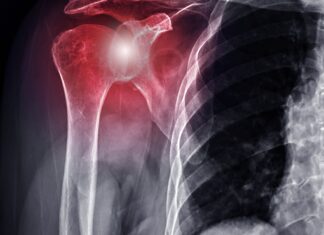

Fibromialgia: l’importanza della riabilitazione e dell’attività fisica

Una delle patologie reumatiche maggiormente diffuse nella popolazione è la fibromialgia, che colpisce principalmente la muscolatura con dolore cronico e diffuso. Con...